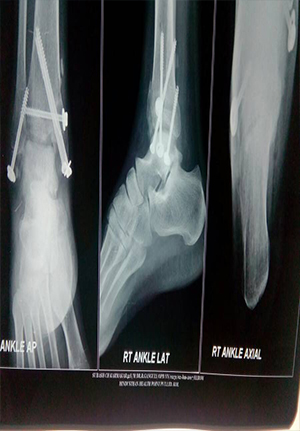

Fracture disocation Ankle treated by ORIF